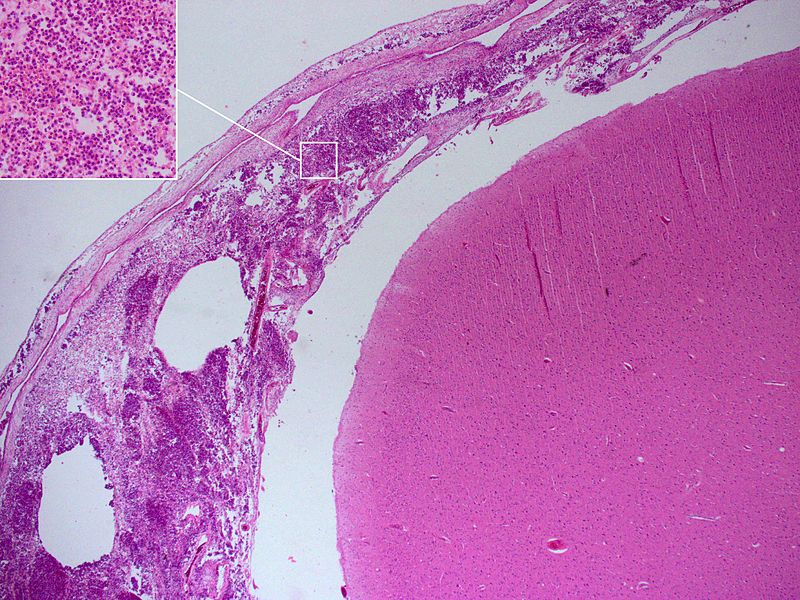

Bacterial Meningitis

- Increased neutrophils

- Decreased glucose

The causative organism may be identified by gram stain, polymerase chain reaction (PCR), Matrix Assisted Laser Desorption/Ionization – Time of Flight (MALDI-TOF), and culture.

The majority of the time, bacterial meningitis has complications.

Potential complications of meningitis include:

- Death due to herniation secondary to cerebral edema

- Seizure(s)

- Hearing loss

- Hydrocephalus